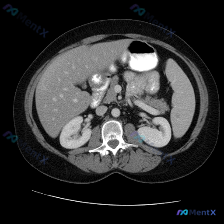

今天看到一张很有意思的上腹部CT软组织窗图像,预设的问题是“找脾脏病变”,但整理完思路发现,这个病例的重点反而不在预设方向上。 --- 先整理一下图像里的客观信息 基础评估 图像质量清晰,对比度适中,无明显运动伪影,层面在上腹部,能看到肝、胃、脾、胰、双肾、腹主动脉这些结构。 各脏器表现 1. 脾脏...

最近看到一份腹部CT平扫的病例资料,最初的关注点被引向了“脾脏病变”,但仔细读完整份影像分析后,发现思路需要完全调整——整理一下这个过程,挺有警示意义的。 --- 先看影像里的客观发现 这份是腹部CT软组织窗横断面的平扫影像: 1. 脾脏:形态正常,实质密度均匀,未见明确占位性病变; 2. 肝脏:轮...

看到一份挺有意思的影像分析资料,整理了一下思路,分享给大家避坑。 原始问题与影像基本信息 - 初始提示:识别图像中的“脾脏病变” - 影像资料:单幅上腹部CT软组织窗横断面图像 - 图像质量:清晰,无明显伪影 客观影像发现(逐脏器梳理) 1. 脾脏(重点核查):轮廓清晰,脾实质密度均匀,未见明显局灶...

整理了一个很有意思的读片资料,先看一下基本情况: 影像资料概况 - 扫描部位:上腹部横断面CT(软组织窗) - 图像质量:清晰,对比度适中,无明显运动伪影 - 显示结构:肝脏、胃、脾脏、腹主动脉、椎体及周围软组织 主要影像描述(按器官整理) - 肝脏:形态轮廓尚平滑,实质密度均匀,未见明显局限性肿块...

最近看到一个读片资料,预设问题是“图像中是否存在脾脏病变”,先和大家理一下完整的思路。 --- 先列一下拿到的「影像客观事实」 这是一幅上腹部CT软组织窗横断面图像: 1. 肝脏:轮廓平整,实质密度均匀,肝内血管走行清晰,无受压移位; 2. 脾脏:划重点——形态正常、大小正常、实质密度均匀,未见局灶...